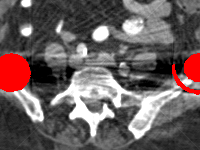

Effect of metal mask projection (SE0-Net vs SE-Net). From Table 1, we can observe the use of instead of improves the performance for at least 4.1 dB in PNSR and reduces MSE from 0.95219 to 0.00074 for all metal sizes. The groups with large metal implants benefit more than groups with small metal implants. As shown in Fig. 4, the artifacts in metal trace of SE0-Net are over-removed or under-removed, which introduces bright and dark bands in the reconstructed CT image. With the help of , SE-Net can suppress the artifacts even when the metallic implants are large and the surrogate data are more consistent with the correct data outside the metal trace.

Effect of sinogram padding (SE-Net vs SEp-Net). Sinogram padding mainly improves the performance in the group with the largest metal objects, with a PSNR gain of 0.15 dB and an MSE reduction of 0.00048. As shown in Fig. 4, the model with sinogram padding restores finer details of soft tissue between large metallic objects because more correct information is retained by periodic padding than zero-padding.

Effect of learning with (SEp-IE-Net vs Ours). When is jointly restored with the corrupted , the sinogram correction performance is affected with an increment of 0.00033 in MSE and of 0.7 dB in PSNR. More details of soft tissue around metal are retained and the image becomes sharper, as shown in Fig. 4.